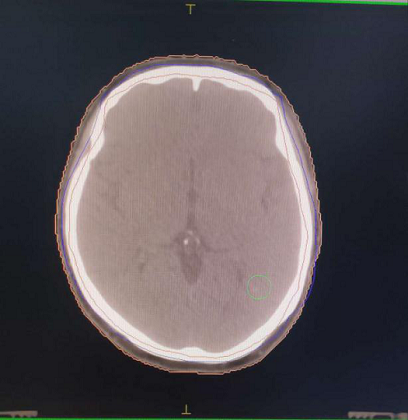

左图为CT图像,右图为图像融合后画面,可以清晰观察到圈内病灶。

在查看患者影像资料后,为进一步提升靶区勾画的精准度,提升放疗疗效,刘冠副主任决定采取CT/MRI图像融合技术为患者进行靶区勾画。在阿克苏第一人民医院放疗科副主任郑光浩、物理师胡东等人的配合下,CT/MRI图像融合技术勾画放疗靶区获成功。

刘冠副主任介绍,为患者制定放疗计划时,需要根据患者影像检查结果来确定肿瘤边界,由于CT与MRI两者的成像原理不同,突出显示的解剖结构也有所不同,但如果通过数据转换,将不同种的影像互相融合在一起,使MRI与CT图像的优势相结合,实现信息互补,便可以精确勾画患者肿瘤区域,为放射治疗方案的确定与临床诊断提供更丰富的信息。此举对精确放射治疗具有重要的研究意义。